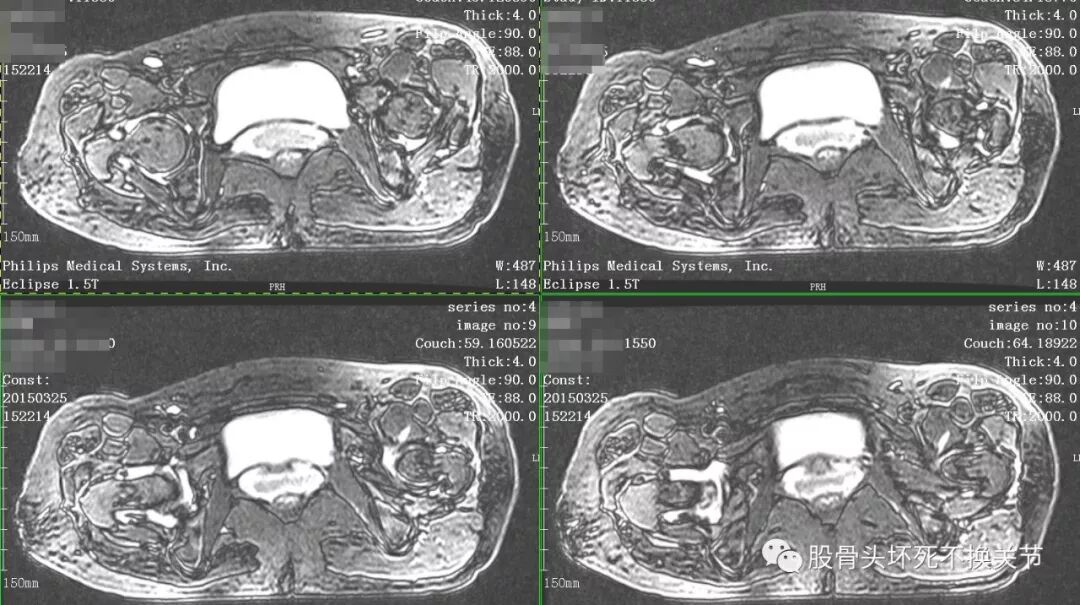

点击放大观看双侧髋关节核磁共振片:

核磁共振检查显示右侧股骨头周围一圈亮度均匀的白色信号,就是平常所说的关节积液。